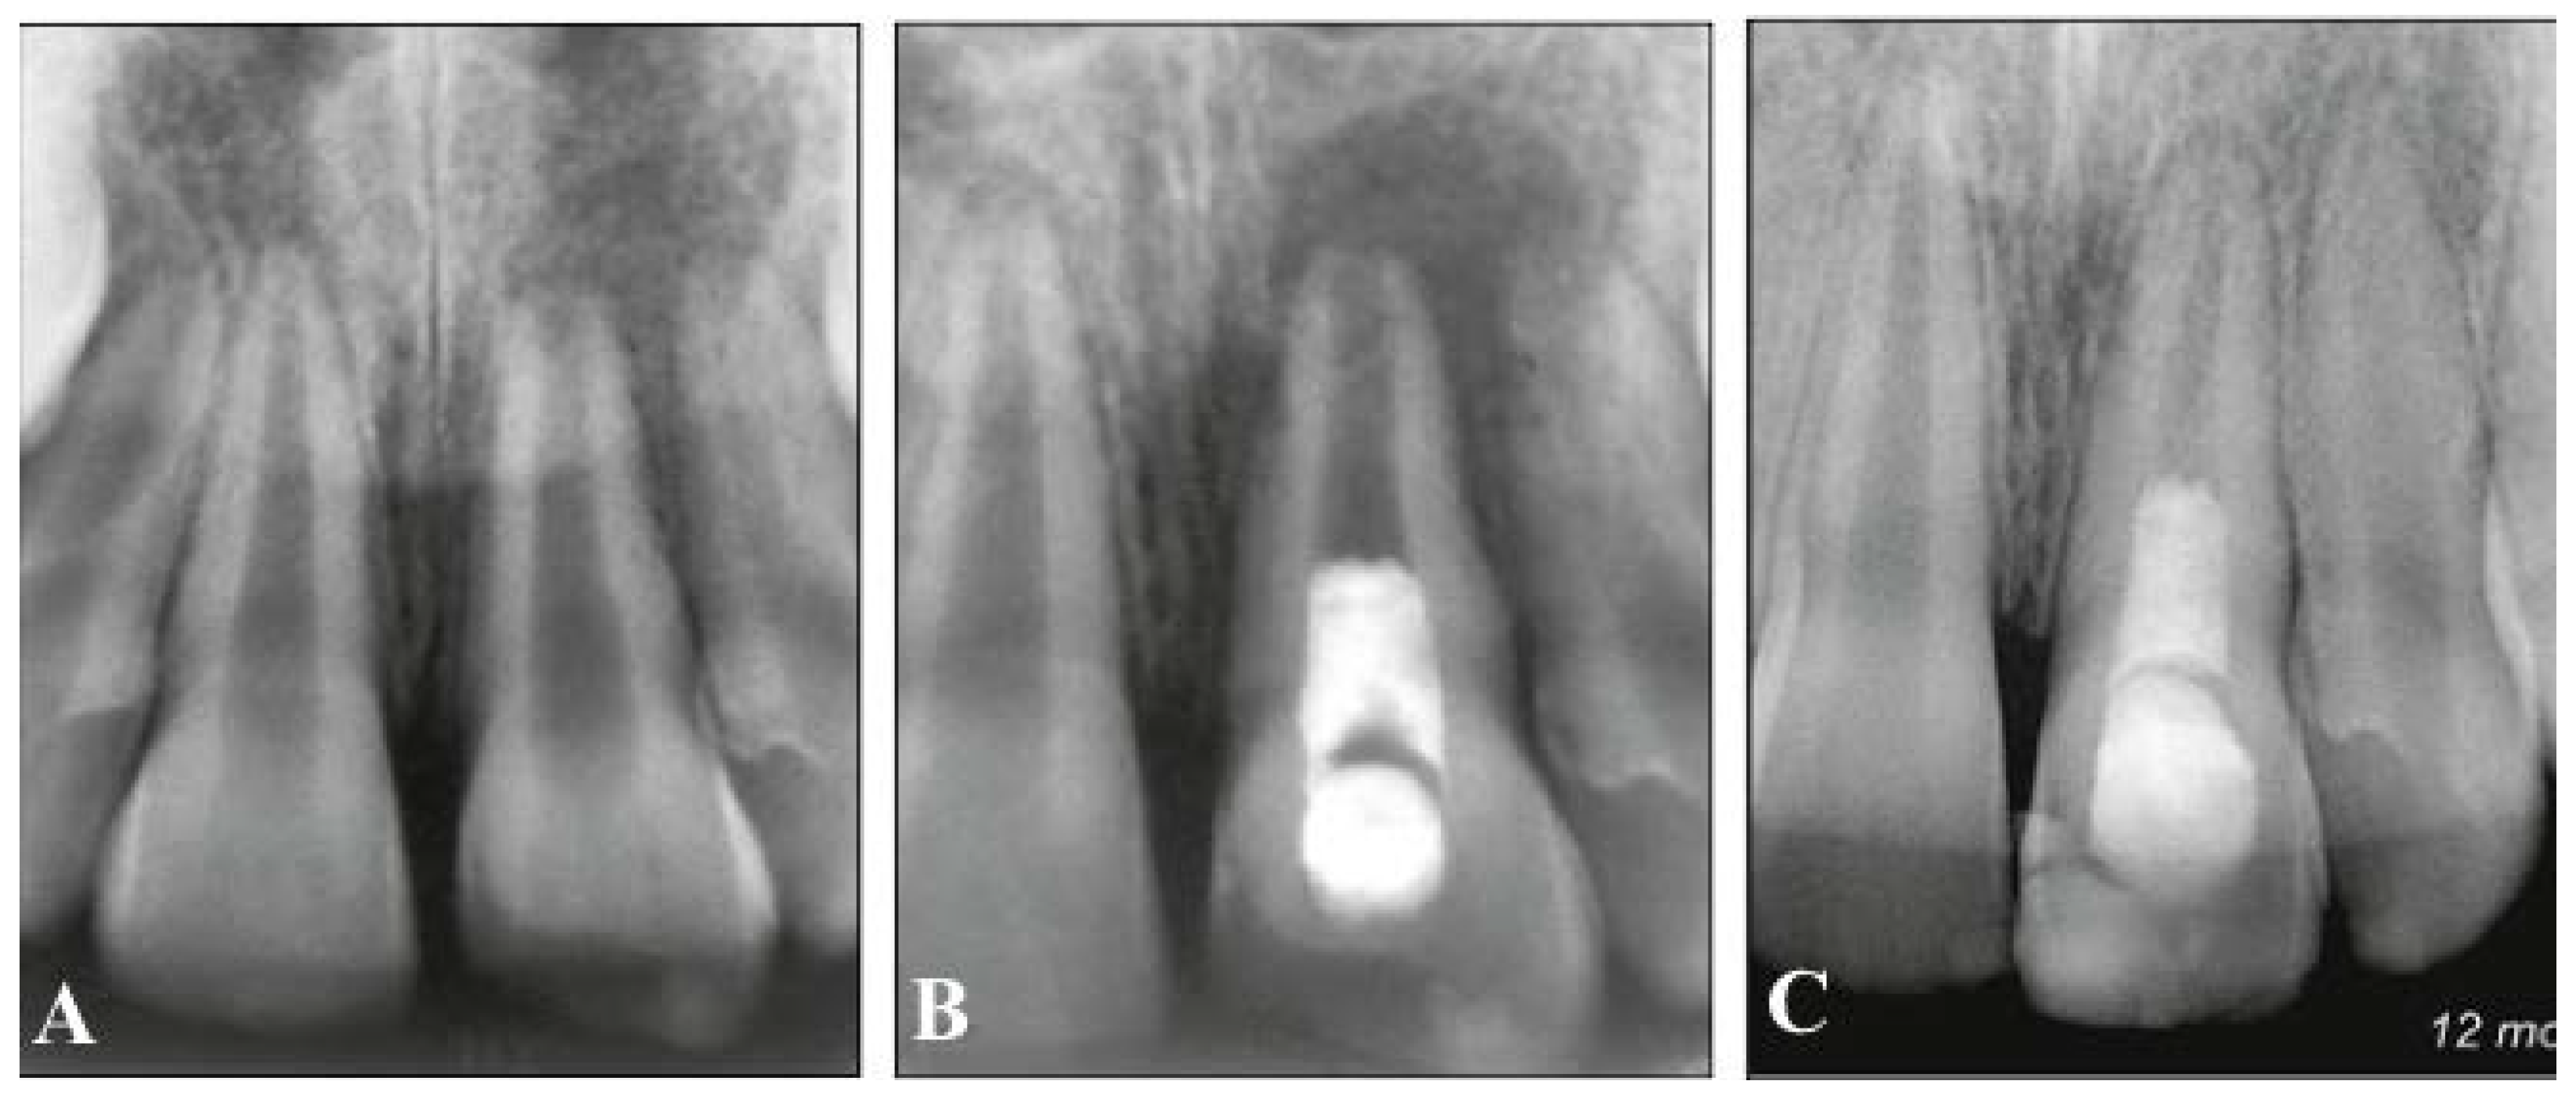

9. Treatment of Mature Permanent Teeth with Necrotic Pulps

- Saoud, T.M.; Martin, G.; Chen, Y.-H.M.; Chen, K.L.; Chen, C.A.; Songtrakul, K.; Malek, M.; Sigurdsson, A.; Lin, L.M. Treatment of mature permanent teeth with necrotic pulps and apical periodontitis using regenerative endodontic procedures: A case series. J. Endod. 2016, 42, 57–65. [Google Scholar] [CrossRef] [PubMed]